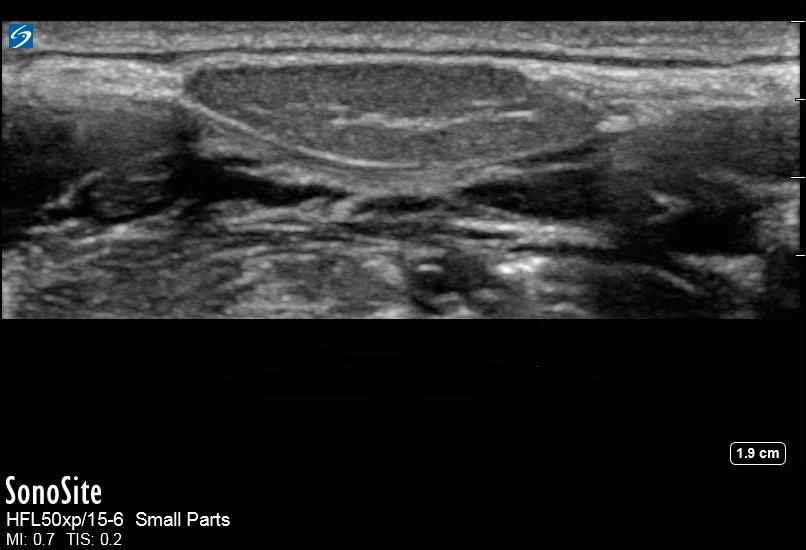

舌下腺图像